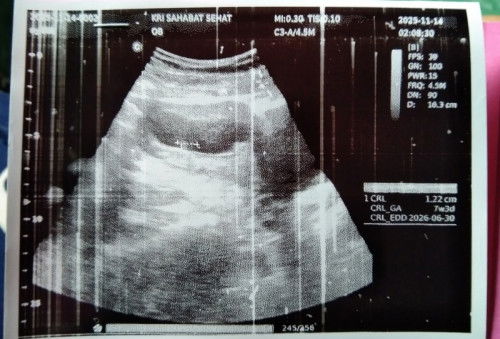

USG 7 week

USG 7 week kata dokternya kantung masih kecil banget tp ada ukuran CRL nya 1, 22cm. Apakah beneran hamil ya bunda" mohon penjelasanya soalnya waktu dijelasin agak ngang ngong maklum baru anak pertama....#mohonbantujawabbunda #Sharingdong_Bund

hamil itu bun. ukuran janinnya udah lumayan itu. udah ada detak jantungnya belum ? soalnya aku 6 week janinny udah ada tp detak jantung belum ada